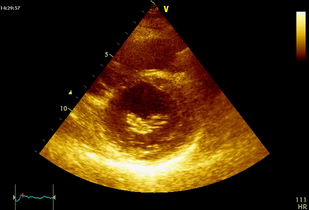

• Обложка: Митральный порок сердца с преобладанием митрального стеноза при системной красной волчанке (рис. 7.8)